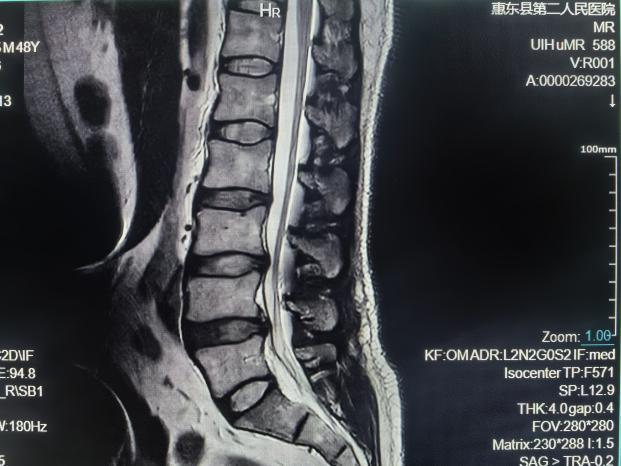

脊柱MRI检查

椎管内肿瘤:包括髓内、外肿瘤、硬膜下肿瘤、硬膜外肿瘤;脊膜膨出和脊髓脊膜膨出;脊髓创伤;硬膜外脓肿和硬膜下脓肿;椎管内血管畸形;脊髓空洞症;脊髓萎缩;⑧椎间盘突出;⑨椎管狭窄。

腰椎间盘突出磁共振成像